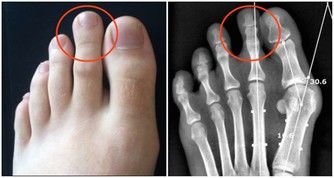

後來到另一家醫院檢查,最後確診為圓錐角膜。

圓錐角膜的最終結果就是角膜移植,

而角膜供體又十分緊張,我的那位朋友現在的感覺是生不如死。